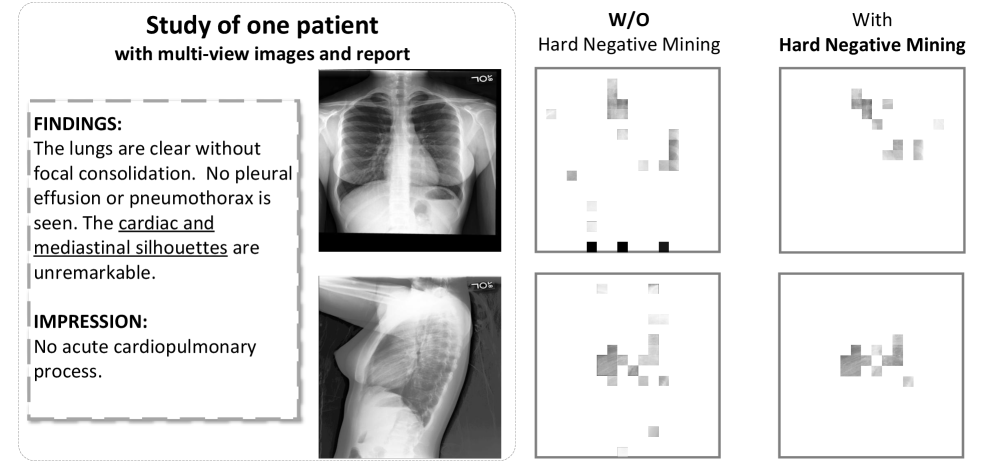

Refer to caption

Figure 4: Visualization of the local-level alignment related to underlined words for the ablative study of hard negative mining.

Ablation for Hard Negative Mining

To show that our approach of hard negative mining benefits model performance on Med-VQA tasks, we first investigate the necessity of using soft labels for global-level alignment. As shown in Tab. 3, the comparison between #7 and #4 indicates that using soft labels boosts the average model performance by 1.37%. We also show that soft labels for global intra-modality alignment facilitates the model’s representation ability by comparing #7 with #5. Moreover, to prove the significance of hard negative pair discrimination, we compare #6 with #5 and #8 with #7. Besides, we also conduct a qualitative ablation study for hard negative mining as shown in Fig. 4, comparing ablations #8 and #4. After hard negative mining, the patch tokens related to the underlined words are more concentrated on regions with possible semantic information, showing that our mining method leads to a more robust modality co-attention module, which yields more interpretable results for local-level alignment.